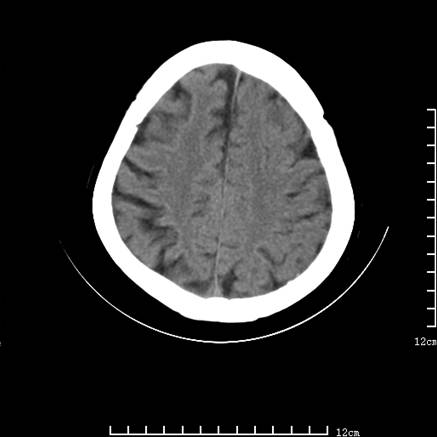

标题: V0514:女,72岁,偶有头晕,自诉记忆力减退,来诊。 [打印本页]

标题: V0514:女,72岁,偶有头晕,自诉记忆力减退,来诊。

2、脑萎缩ct表现。

垂体腺瘤可能性大!另:轻度脑萎缩!

考虑垂体腺瘤可能性大。脑萎缩。

考虑------垂体腺瘤可能性大----脑萎缩

考虑垂体腺瘤可能性大。脑萎缩。  建议mri 检查